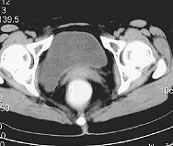

三、輔助檢查

(1)B超檢查:可以顯示子宮腫瘤內部結構、邊緣情況以及低阻血流信號等。